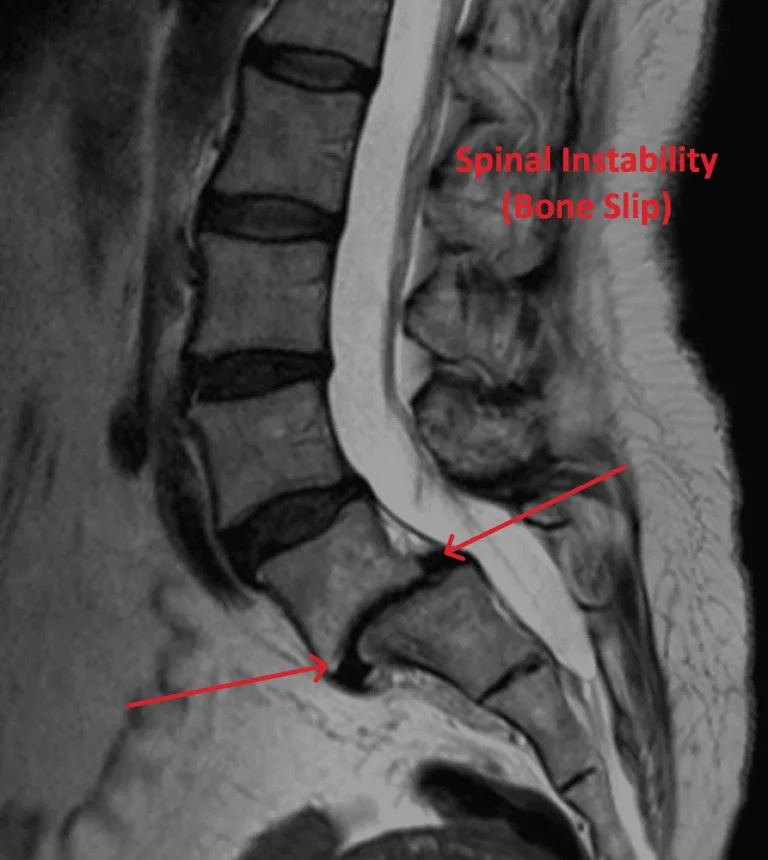

MRI showing spinal instability with highlighted bone slip.

Spinal Instability